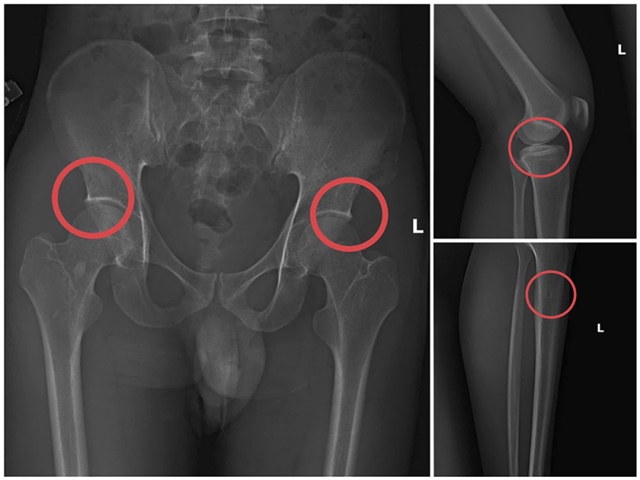

truc-loi-bao-hiem-3

Bản phim chụp XQ một số tổn thương xương do đối tượng Tạ Minh Châu tạo ra.